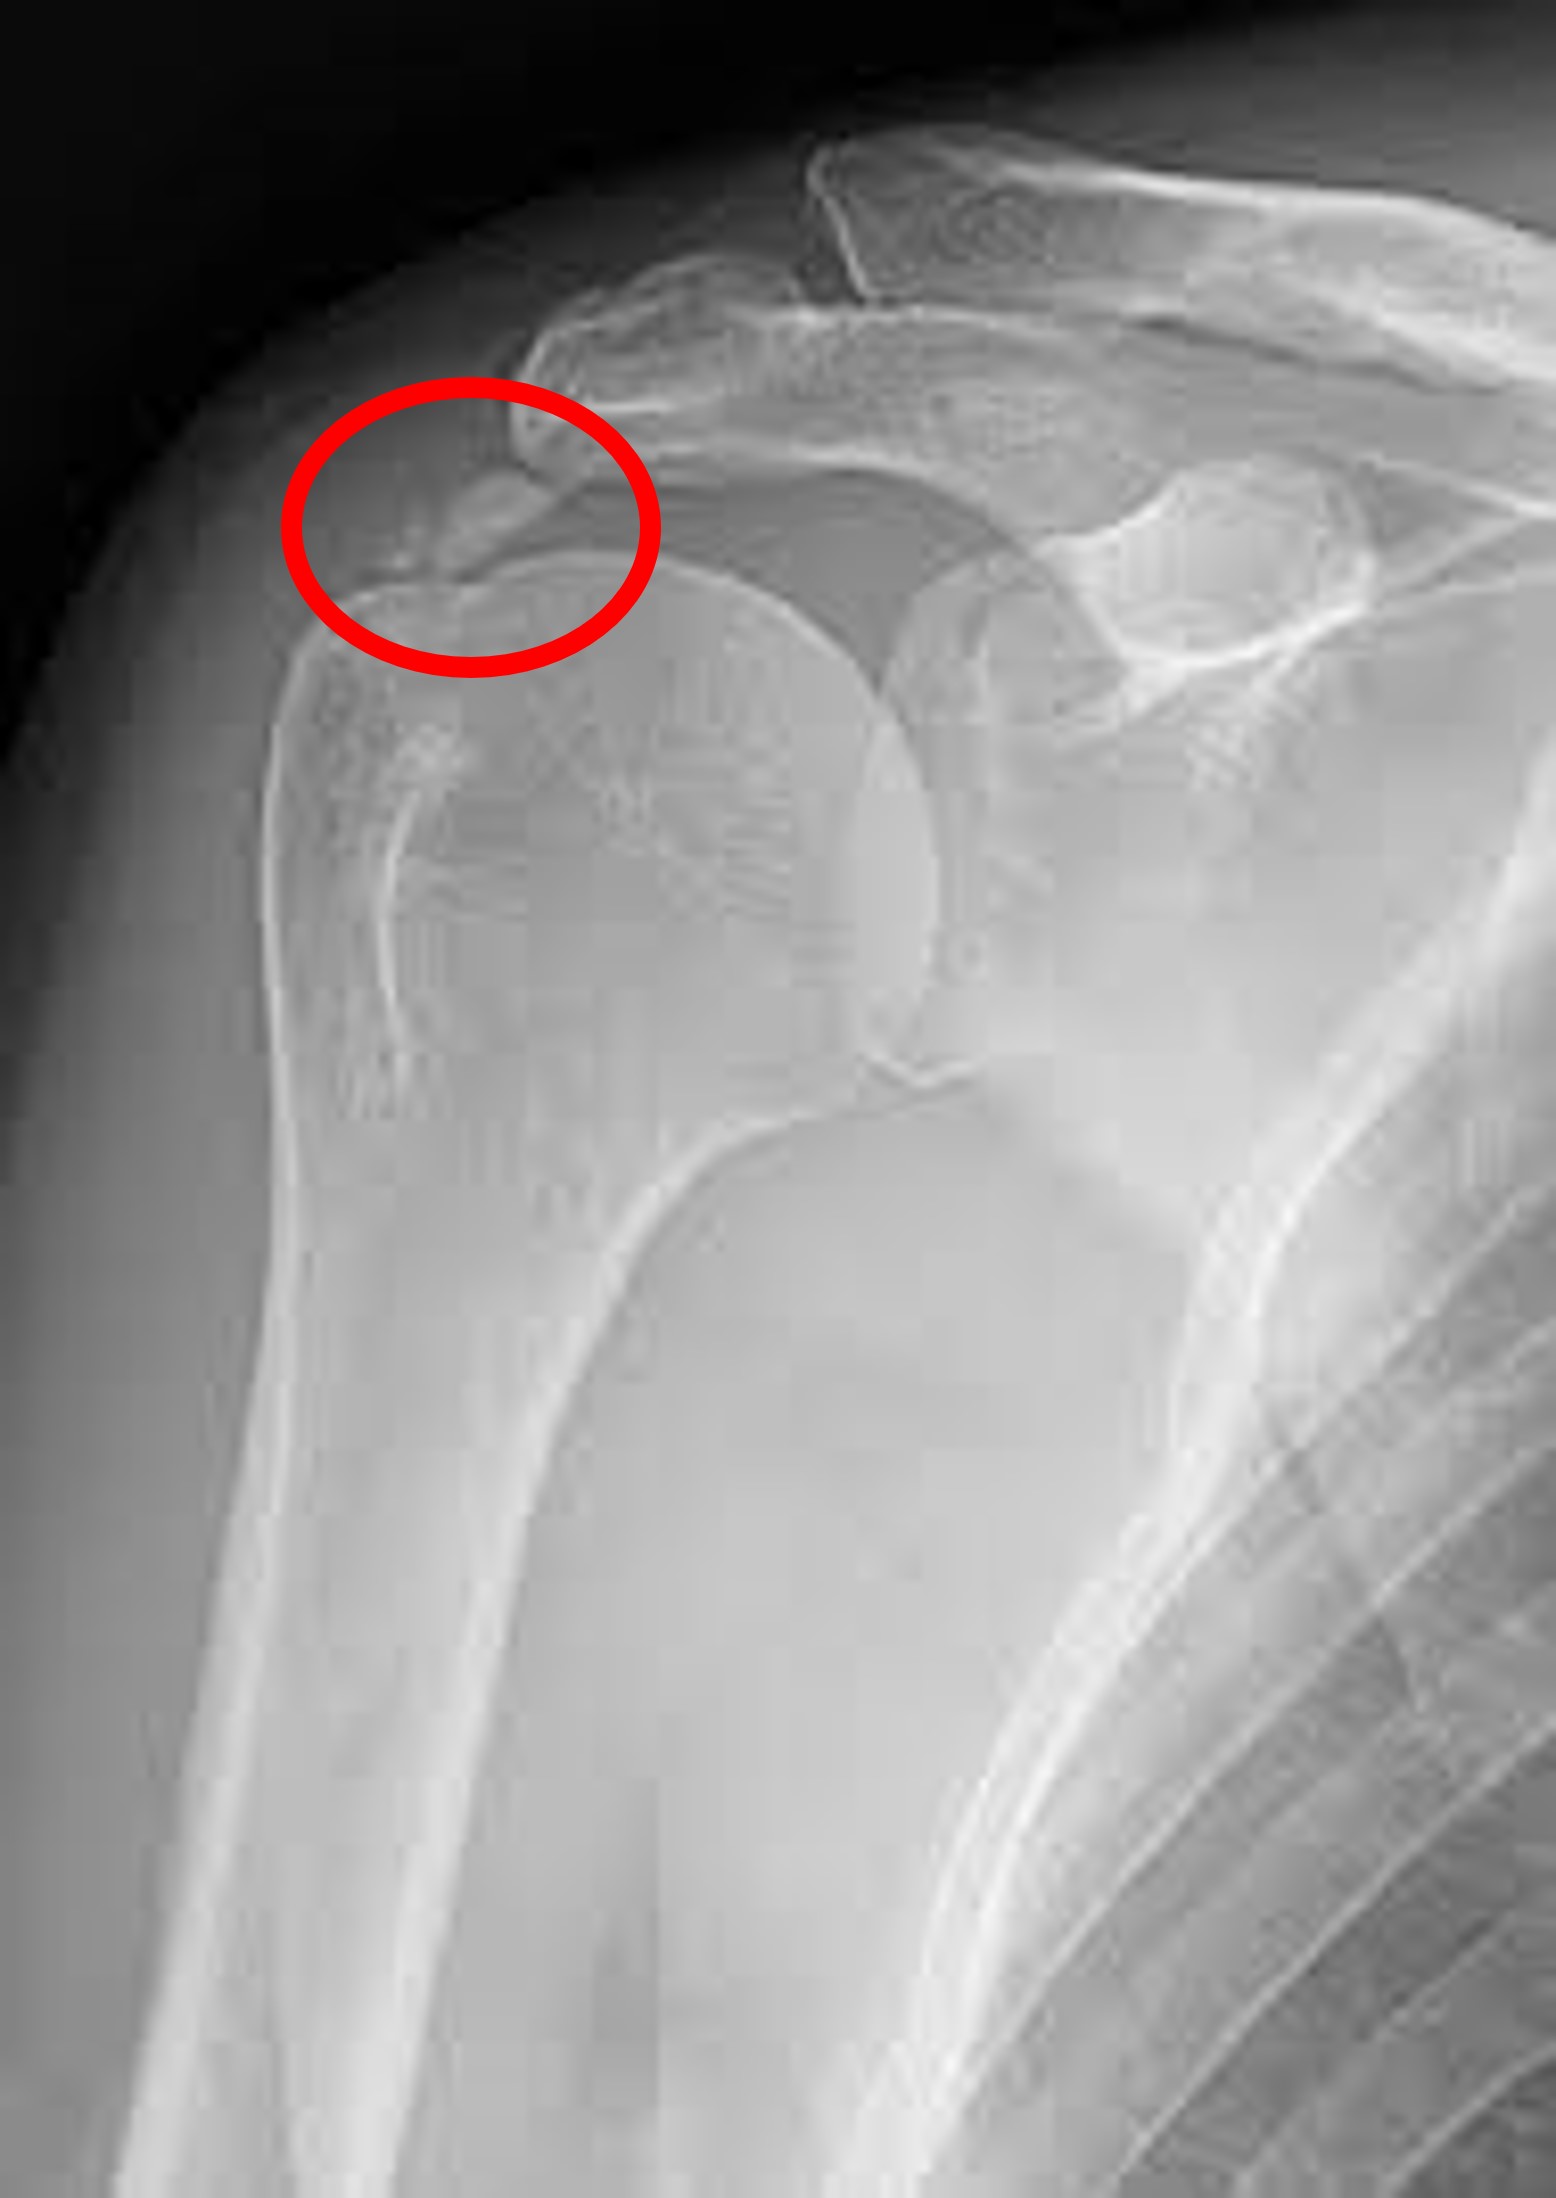

1. X-ray 검사 :

정형외과에 방문하시게되면 가장 많이 하시게 되시는 검사입니다. 가장 기본적이면서도 가장 먼저 감별해야할 위험한 진단을, 예를 들면 골절이나 골종양 등을 발견할 수 있게 해주는 값싸고도 고마운 검사입니다.

동결건에서 X-ray는 사실 진단에 큰 역할을 하기보다는, 그 기저 질환이 무엇인지 알아낼 수 있는 장치로써, 기본적으로 촬영하게 되는 검사입니다.

앞에서 말씀드린 이차성 동결건의 원인 중 하나인 석회성 건염이 있는지를 감별하게 해주며, 관절염이 심하게 진행되신 분들도, 단순 엑스레이 검사를 통해서 감별이 가능합니다.

그러니 병원 방문 전 어느정도 동결건에 대해서 인터넷으로 검색해보고 가셨다고 하시더라도, "X-ray로 별거 안보이는데 왜 찍나요? 돈벌려고 하는거 아닌가요?"라는 말씀은 하지 말아주세요 ^^;;